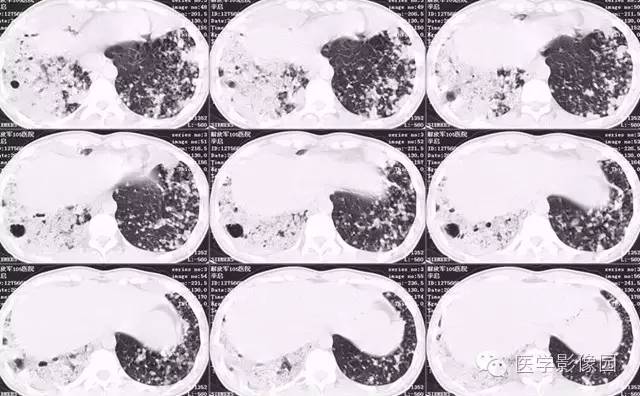

弥漫性肺泡细胞癌1例CT影像表现

病理结果:弥漫性肺泡细胞癌

弥漫性肺泡癌的主要临床及CT表现:临床表现无明显特征, 随着病情的进展, 咳嗽、 咳白痰、 进行性气促。CT表现 为病变分布有两种情况:病变累及一个肺段或肺叶;病变广泛分布于两肺。可归纳为5个特征性征象:蜂房征;支气管充气征;磨玻璃征;血管造影征;两肺弥漫分布的斑片状与结节影。